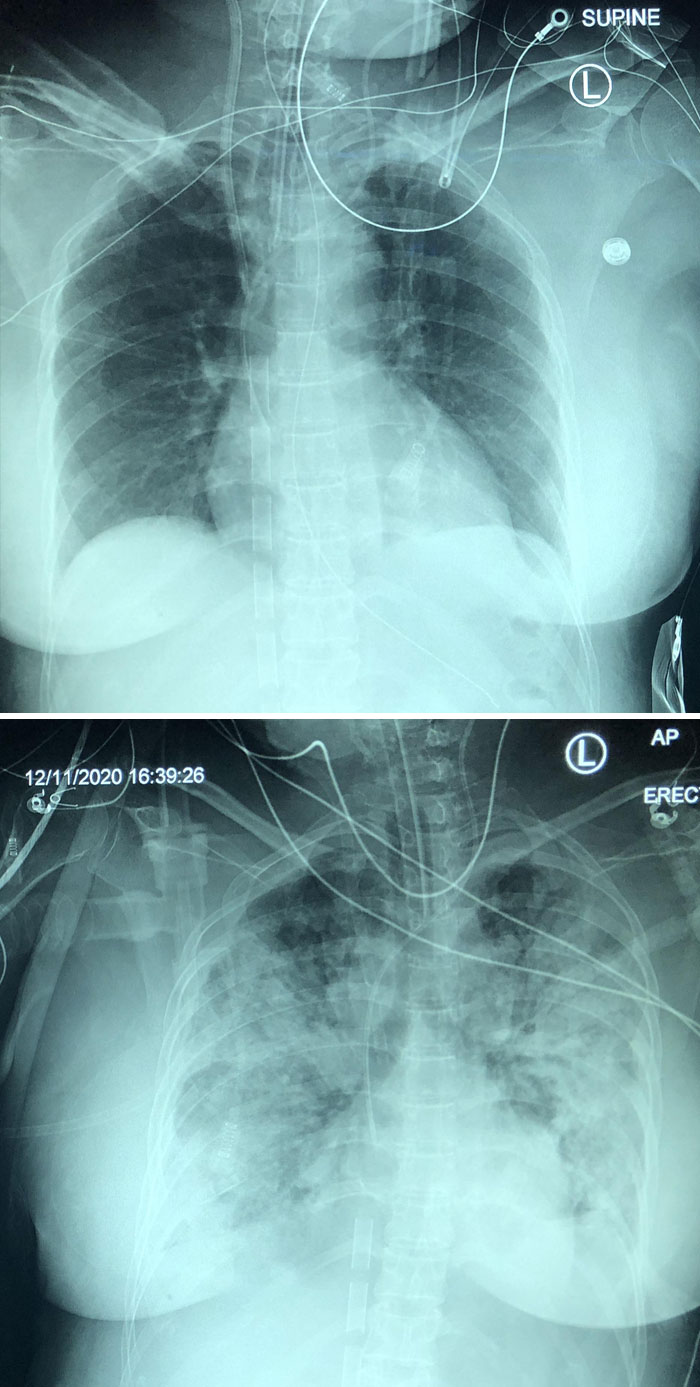

5-дневное прогрессирование пневмонии, вызванной коронавирусом